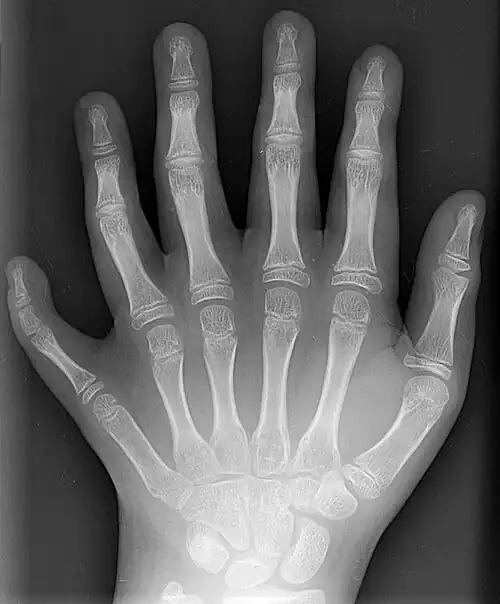

Bones

The skeleton of the human hand consists of 27 bones:[10] the eight short carpal bones of the wrist are organized into a proximal row (scaphoid, lunate, triquetral and pisiform) which articulates with the bones of the forearm, and a distal row (trapezium, trapezoid, capitate and hamate), which articulates with the bases of the five metacarpal bones of the hand. The heads of the metacarpals will each in turn articulate with the bases of the proximal phalanx of the fingers and thumb. These articulations with the fingers are the metacarpophalangeal joints known as the knuckles. At the palmar aspect of the first metacarpophalangeal joints are small, almost spherical bones called the sesamoid bones. The fourteen phalanges make up the fingers and thumb, and are numbered I-V (thumb to little finger) when the hand is viewed from an anatomical position (palm up). The four fingers each consist of three phalanx bones: proximal, middle, and distal. The thumb only consists of a proximal and distal phalanx.[11] Together with the phalanges of the fingers and thumb these metacarpal bones form five rays or poly-articulated chains.

There are numerous sesamoid bones in the hand, small ossified nodes embedded in tendons; the exact number varies between people:[7] whereas a pair of sesamoid bones are found at virtually all thumb metacarpophalangeal joints, sesamoid bones are also common at the interphalangeal joint of the thumb (72.9%) and at the metacarpophalangeal joints of the little finger (82.5%) and the index finger (48%). In rare cases, sesamoid bones have been found in all the metacarpophalangeal joints and all distal interphalangeal joints except that of the long finger.

Additional images

X-ray showing joints -

Hand bone anatomy